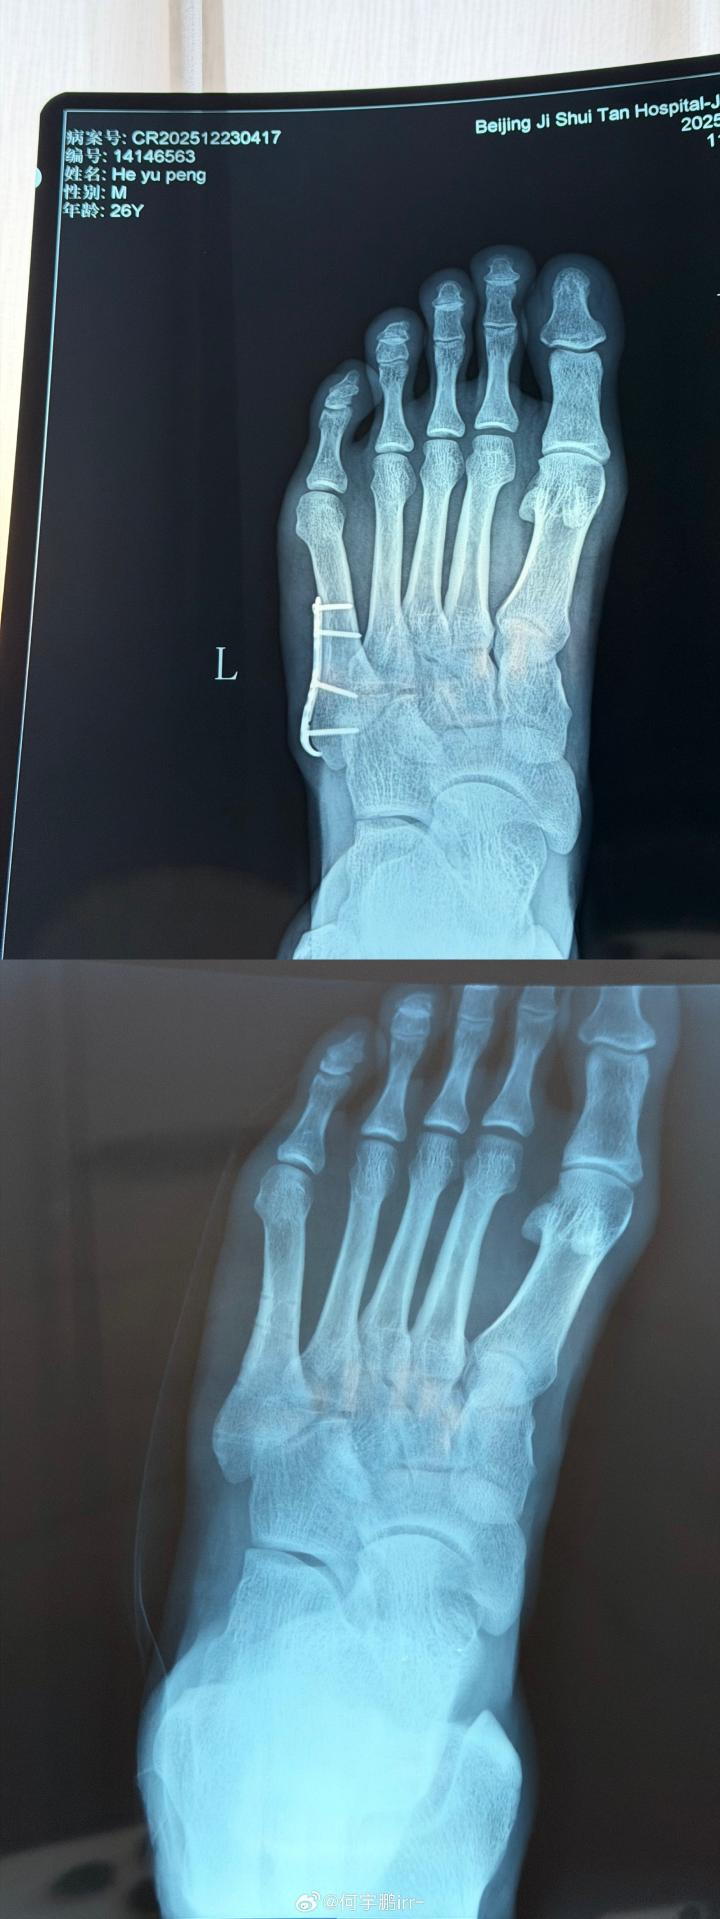

北京时间12月25日,北京国安球员何宇鹏在社交媒体上分享了自己摘除左脚钢板的照片。

何宇鹏写道:“终于要和身体里这个‘铁哥们’说再见了

虽说为了你足球鞋都大了半码哈哈哈!但也非常感谢8个月的保驾护航,现在,是时候说再见了! 从一开始不敢置信可以带着钢板踢球,到二次手术圆满结束,都不得不提我的大功臣,感谢积水潭孙旭主任用超高的医术精密地修补了我的身体! 也感谢葆石头康复与@掰腿老黄 的鼎力支持!愿每一次伤愈都能变得更坚韧!”